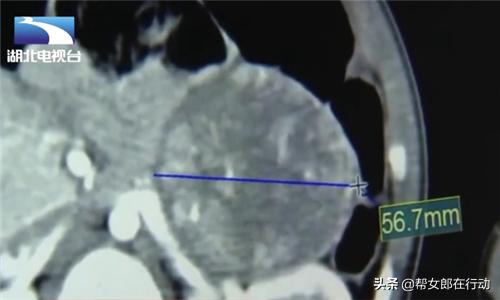

医生介绍说:“当地医院做了个B超提示,发现是肾上腺长了个肿块,然后跑到我们这边来,明显发现这个小男孩的激素含量很高,然后做了一些ct之类的检查,发现肾上腺有5公分多的一个肿块在那个地方,那么就可以确认是一个肾上腺的肿瘤,因为肿瘤分泌异常多的激素,导致他男孩子向女性化发展。”